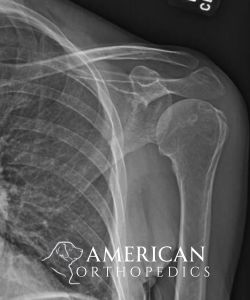

Total Shoulder Replacement

Patient of Dr. Ratner.

Before